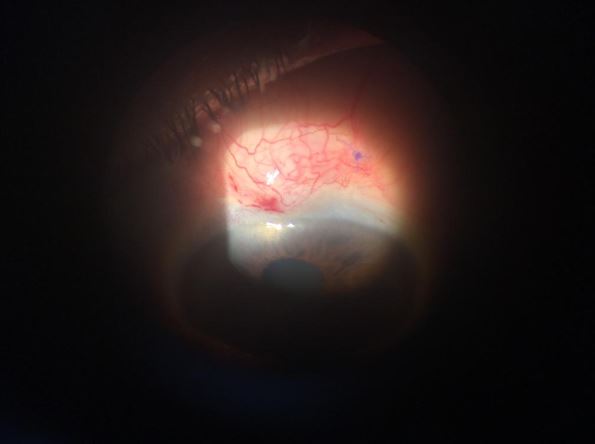

Cirugía de Glaucoma con implante Valvular

Existen actualmente varios tipos de válvulas que son dispositivos de drenaje del Humor Acuoso. Se colocan sobre la superficie ocular y poseen un tubo que es el encargado de tomar del ojo el líquido en exceso y llevarlo a la válvula para que sea liberado también a la circulación ocular. Este tipo de cirugías está indicado cuando la presión ocular está muy alta y no es posible bajarla con otros procedimientos, también en casos de un tipo de Glaucoma llamado Neovascular y en ojos ciegos con presiones oculares muy altas, para evitar que se descompense el ojo.